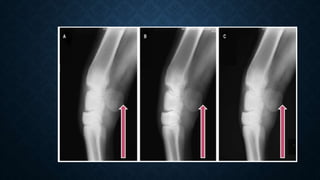

DISTORTED OR BLURRED RADIOGRAPHIC

IMAGE

• Causes:

a) Blurred image due to motion of patient, X-ray tube or cassette during

exposure.

b) Distorted image due to i) poor film-screen contact, ii) improper centering of

the primary beam, and iii) central beam being not perpendicular to the cassette.

• Prevention:

a) Avoid motion.

b) i) Clean intensifying screen.

ii) Correct inadequately moulded screen.

iii)Check proper centering of the central beam.

DISTORTED OR BLURREDRADIOGRAPHIC IMAGE • Causes: a) Blurred image due to motion of patient, X-ray tube or cassette during exposure. b) Distorted image due to i) poor film-screen contact, ii) improper centering of the primary beam, and iii) central beam being not perpendicular to the cassette. • Prevention: a) Avoid motion. b) i) Clean intensifying screen. ii) Correct inadequately moulded screen. iii)Check proper centering of the central beam.